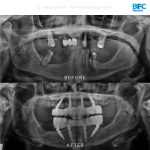

เคสรากเทียมทั้งปาก

รากเทียมทั้งปากด้วยระบบ Digital พร้อมมีฟันใหม่ได้ภายใน 1 วัน